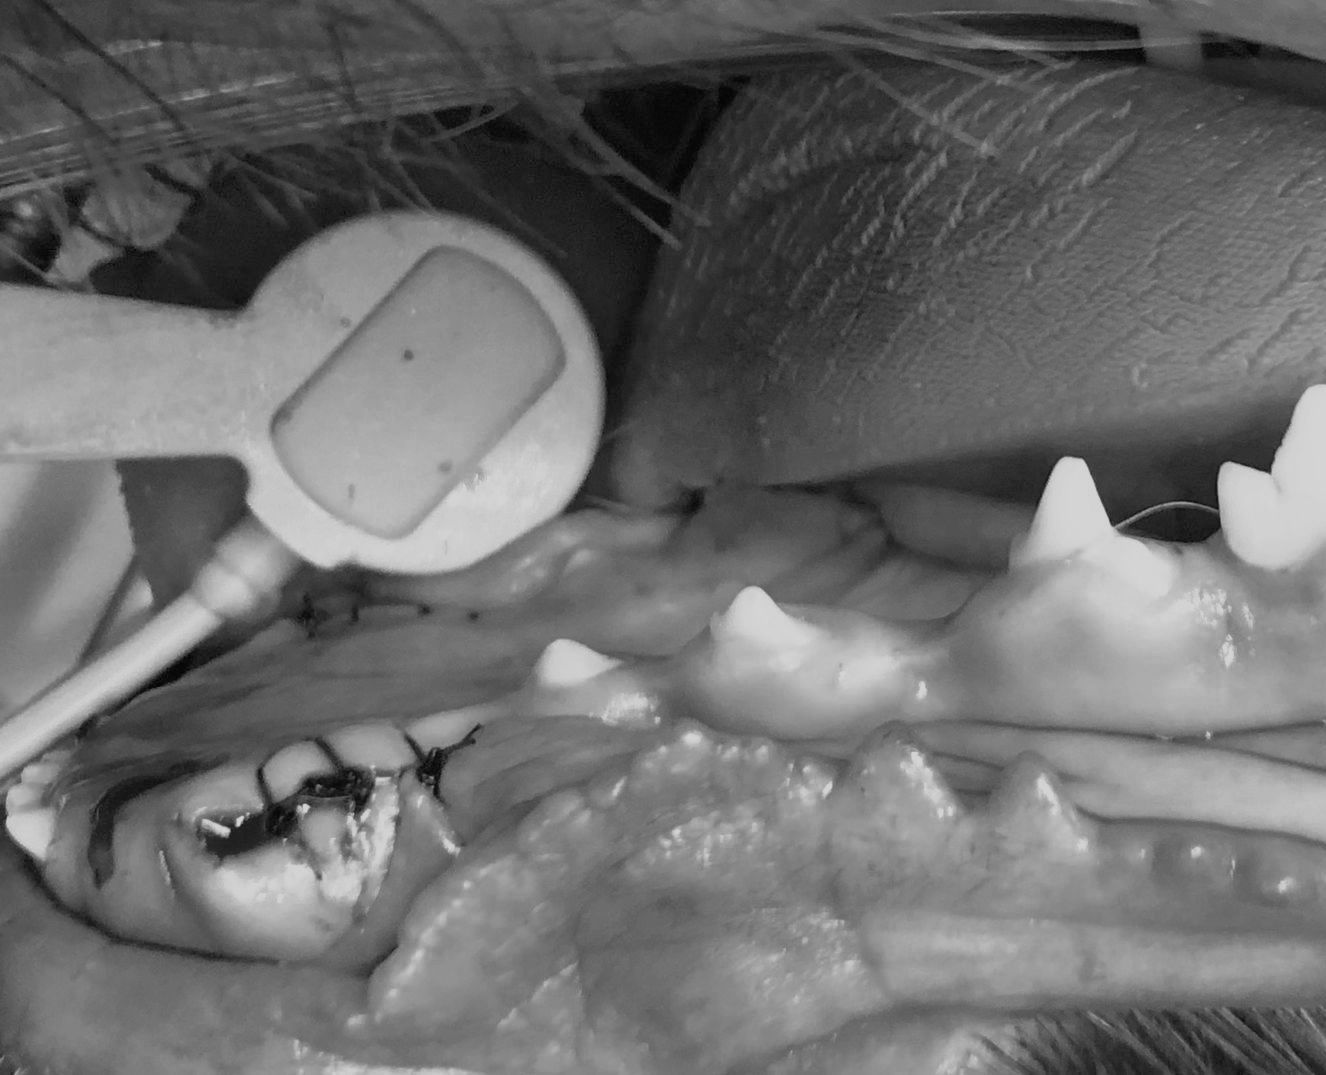

Chirurgische behandelingen

- Chirurgische extracties

-Wortelkanaalbehandelingen